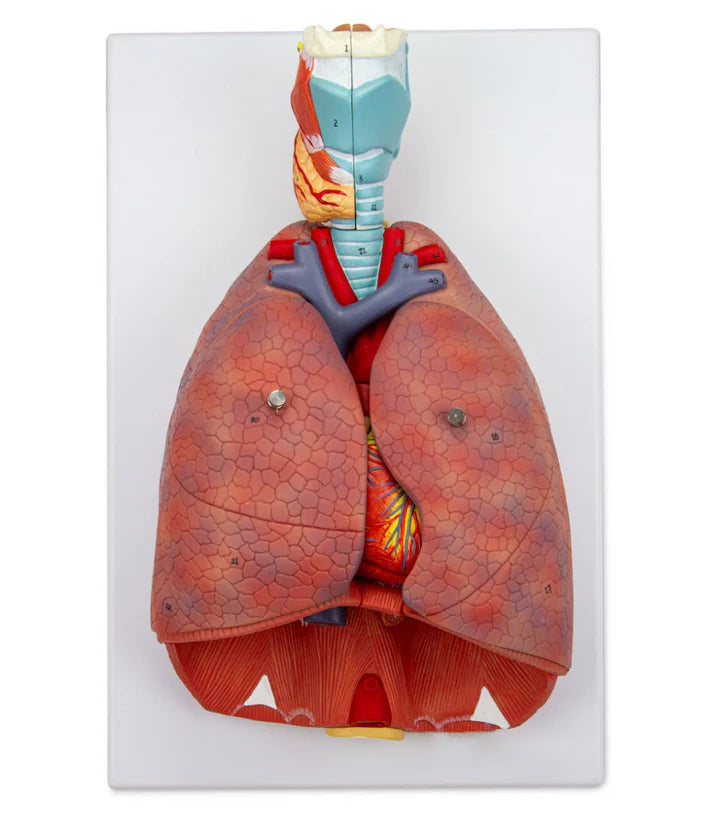

Órganos internos: corazón, pulmones, hígado, riñones, sistema digestivo y reproductivo.